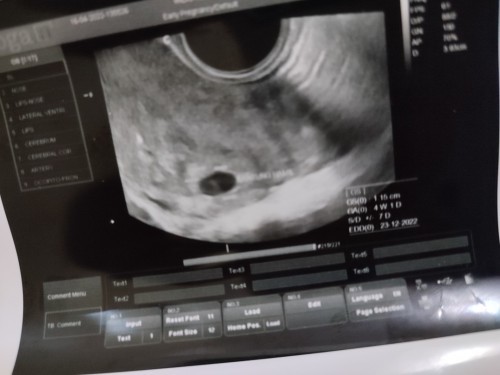

Bun, adakah yang sama divonis BO? Ini aku USG pertama terdeteksi 4w1D eh periksa sebulan kemudian masih kantong aja sama sack yg buat makannya janin itu, cm blm ada janinnya 🥺Usia kehamilan pun cm naik dikit jd 5w5d. Padahal udh jarak sebulan. Dibilang gak berkembang dan harus kuret gtu. Padahal gak ada flek atau gejala buruk lainnya. Apakah masih bs menunggu dengan riwayat 2x USG gtu, apakah ada kemungkinan nanti usia 13w ada janin? Aku pernah BO sebelumnya jd skrg worry banget... 🥲#seriusnanya Terlampir foto awal USG dan USG yang baru td bgt aku lakuin... #ingintahu #pleasehelp

Moms, mgkn ada yang punya pengalaman sama dan bs sharing di sini. Aku lg hamil lagi, klo dari HPHT 6w2d tapi pas USG 4w1d. Masih wajar, cm aku takut BO lagi (aku BO dan kuret 6 bulan lalu). Sama dokter dikasih obat penguat kandungan microgest 200mg. Wajar katanya blm ada janinnya skrg Cuma aku td lupa nanya untuk susu dan vitamin lainnya. Krn sebelumnya aku cuma minum folamil genio mom. Menunggu 1 bln ke depan rasanya was-was takut gak berkembang, walau ttp coba positif thingking sih. #seriusnanya #hamilBO